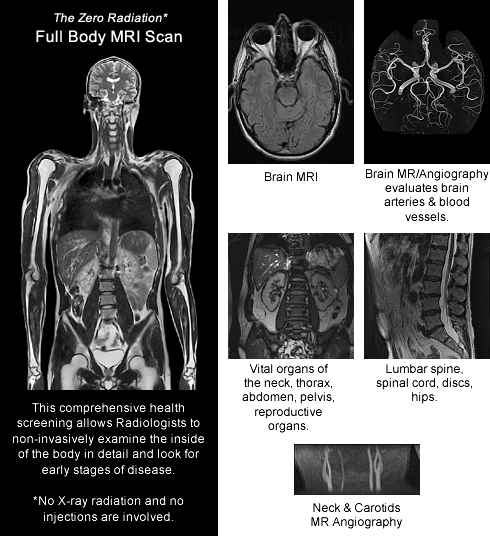

Full Body MRI Scan – Prevenium – MRI Scanning, Screening, MRI Full Body …

Too Much Fat? Try a Whole-Body Scan – WSJ